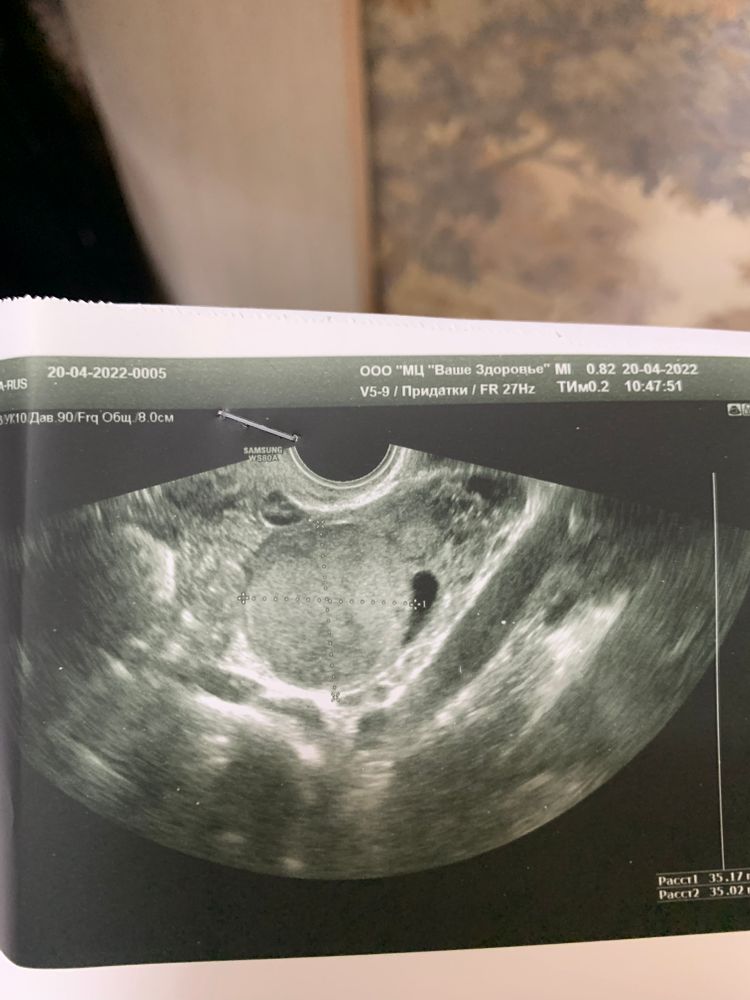

Киста ЖТ или лютеиновая киста

ПЯ - киста жт 30 мм ; фолликул 24 мм( сказали вот вот лопнет )

ЛЯ- киста жт или лютеиновая киста 35 мм; жт 25 мм.

кидаю фото кисты жт или лютеиновой.

подскажите если все такие это не жт, а лютеиновая киста , это не опасно , она уйдёт же ?